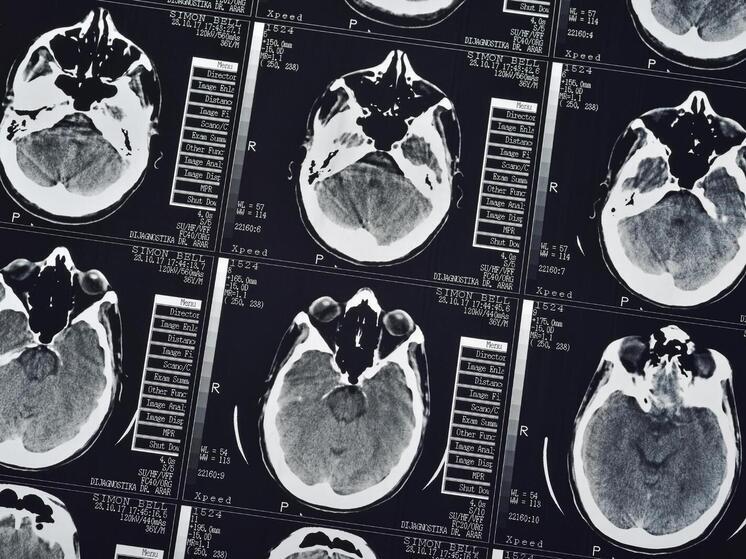

Ученые выявили способность мозга выбирать место для включения «обезболов»

Новое исследование раскрыло пространственную организацию системы плацебо-аналгезии в стволе мозга Ученые из Сиднейского университета впервые составили детальную «карту боли» в стволе головного мозга, обнаружив, что механизм обезболивания плацебо